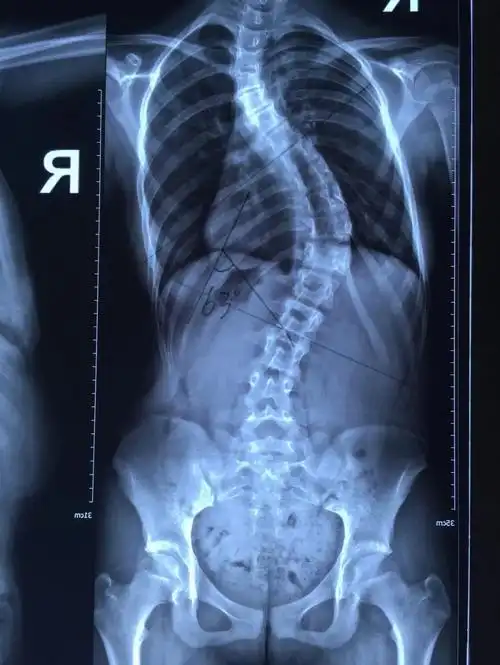

[精] 脊柱弯曲,你叫我如何有个美好的童年!

行走的艺术,凝固的音乐--典型病例:10岁女孩,先天性脊柱侧凸,截骨矫形

最近完成的一例特发性脊柱侧弯

脊柱弯曲角度≥10度就被定义为脊柱侧弯

12岁女孩脊柱侧弯,"惠人 大兴"联合实施全脊柱矫形术

11岁女孩脊柱弯成了"s"型,青少年脊柱侧弯值得关注